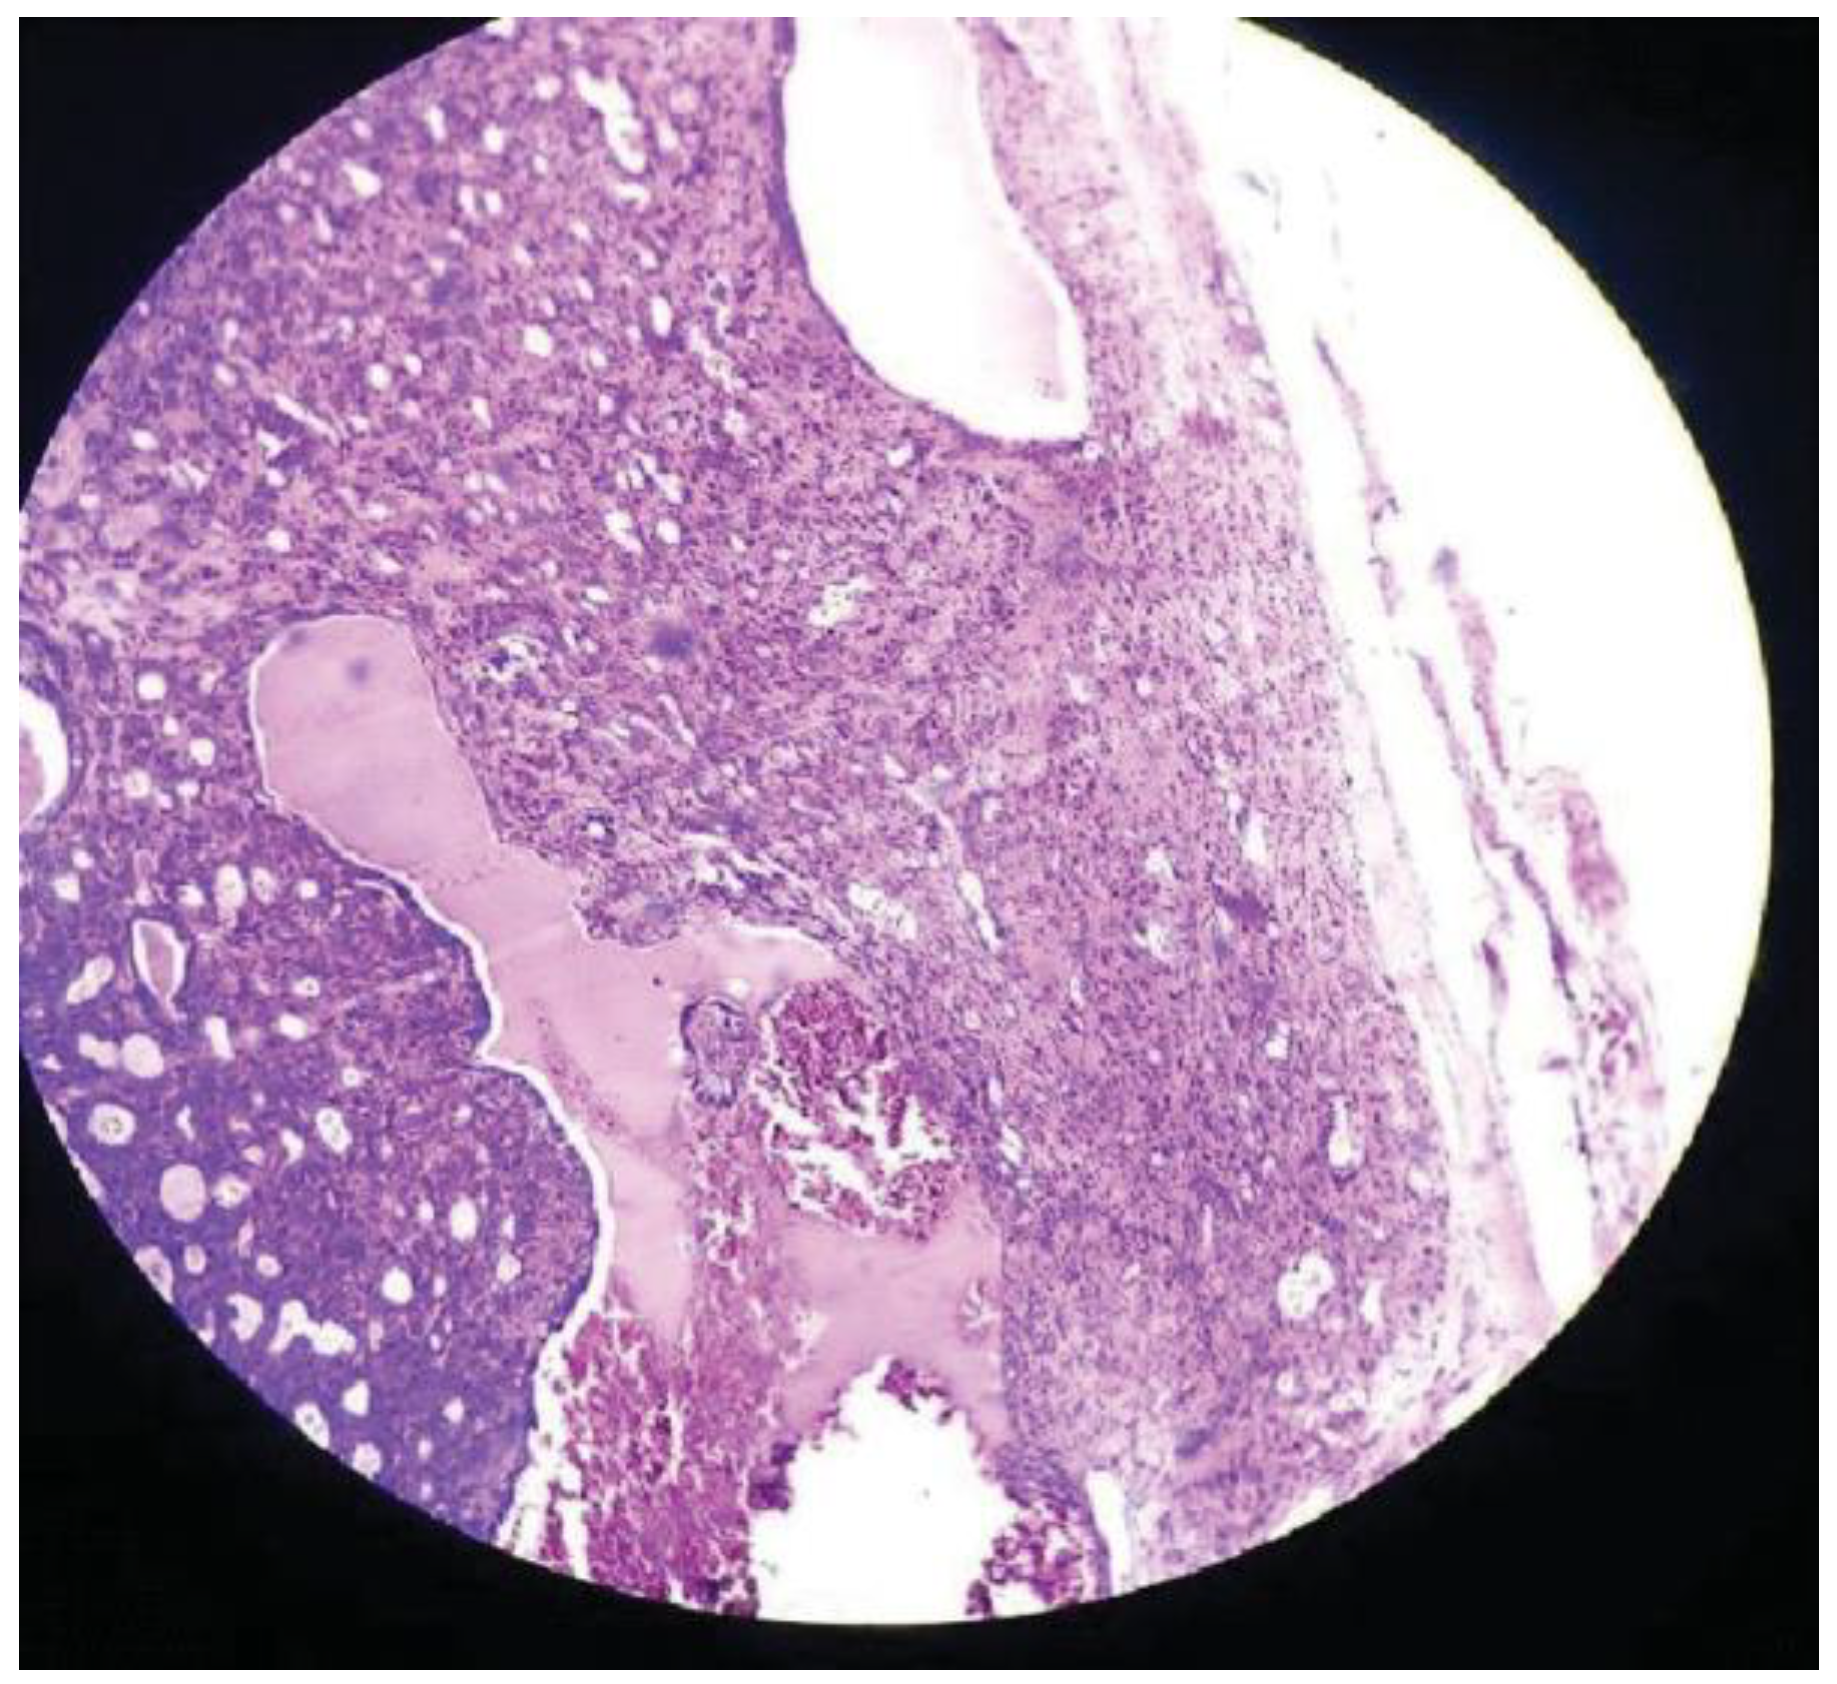

:Case Presentation

Discussion